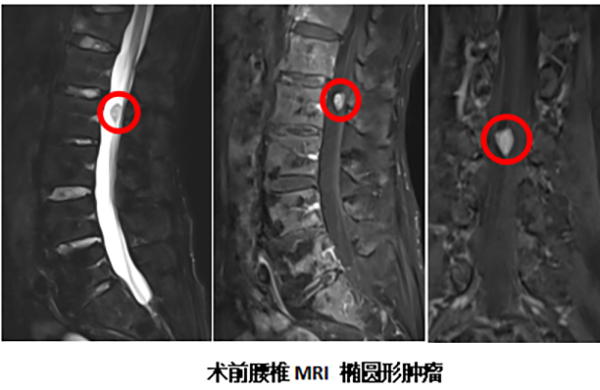

近日,北京怀柔医院神经外科成功诊治了这样一例病例。一位70多岁的患者,长期被慢性腰部疼痛所折磨,且这种疼痛的性质颇为特殊,它不仅局限于腰部,更向身体两侧的肋骨区域放射。这种“不按常理出牌”的疼痛模式引起了患者的警觉,遂前往骨科就诊。经过详细的腰椎核磁共振(MRI)检查,真相浮出水面:导致疼痛的根源并非普通的腰椎间盘突出或腰肌劳损,而是腰椎椎管内长了一个“占位性病变”,也就是我们常说的肿瘤(多为良性),它压迫了支配感觉的神经根,从而引发了奇异的放射痛。

明确诊断后,患者转入神经外科接受进一步治疗。神经外科行政副主任(主持工作)丁小明带领团队对患者病情进行了深入评估,最终决定为其实施手术。与传统手术相比,丁小明团队秉承“精准微创”的现代神经外科理念,创新性地采用了“半椎板入路”手术方式。这意味着医生仅需切除一侧的部分椎板骨质,便能建立一个足够的手术通道,精确抵达并完整切除肿瘤。 这种术式的最大优势在于,极大地保留了对侧椎板及韧带结构的完整性,如同打开一扇“小窗”解决问题,而非拆掉“一整面墙”,从而最大限度地保护了腰椎的力学稳定性,有效避免了术后脊柱失稳、长期腰背痛等传统手术可能带来的并发症。术后,患者恢复迅速,困扰多时的放射性疼痛症状立即显著缓解,取得了立竿见影的治疗效果。